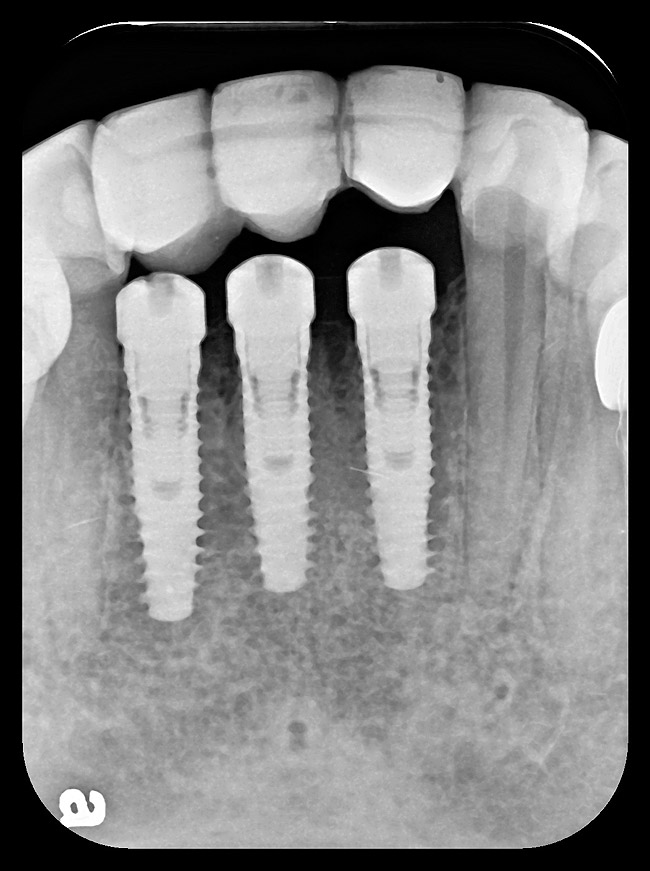

Figure 9: Implants supporting zirconia abutments and crowns, site Nos. 24 through 26—periapical view.

Figure 9

After the zirconia abutments were torqued to 20 Ncm, cotton and composite were used to cover the screw access openings. Figure 7 and Figure 8 show the finished feldspathic porcelain crowns on implants in sites Nos. 24 through 26, and on teeth Nos. 22, 23, 27, and 28; all crowns were cemented with dual-cure resin cement. Good remodeling of gingival architecture is also apparent in Figure 7. As predicted, the free gingival margin (FGM) on No. 23 is approximately 2 mm coronal to those of the adjacent implant crowns on Nos. 24 through 26 (Figure 7); as per the patient’s initial statement, this discrepancy was not an esthetic concern to her. Figure 9 shows the final post-restoration periapical view.